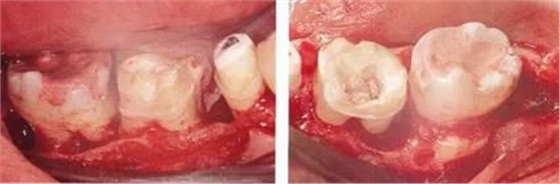

▲圖11-3,4

▲圖11-3,4 齦瓣剝離翻開(kāi)的狀態(tài)。右下6的遠(yuǎn)中牙根有較深的骨組織缺失,右下7的頰側(cè)有II度根分叉病變和近遠(yuǎn)中側(cè)有垂直型骨組織缺失。